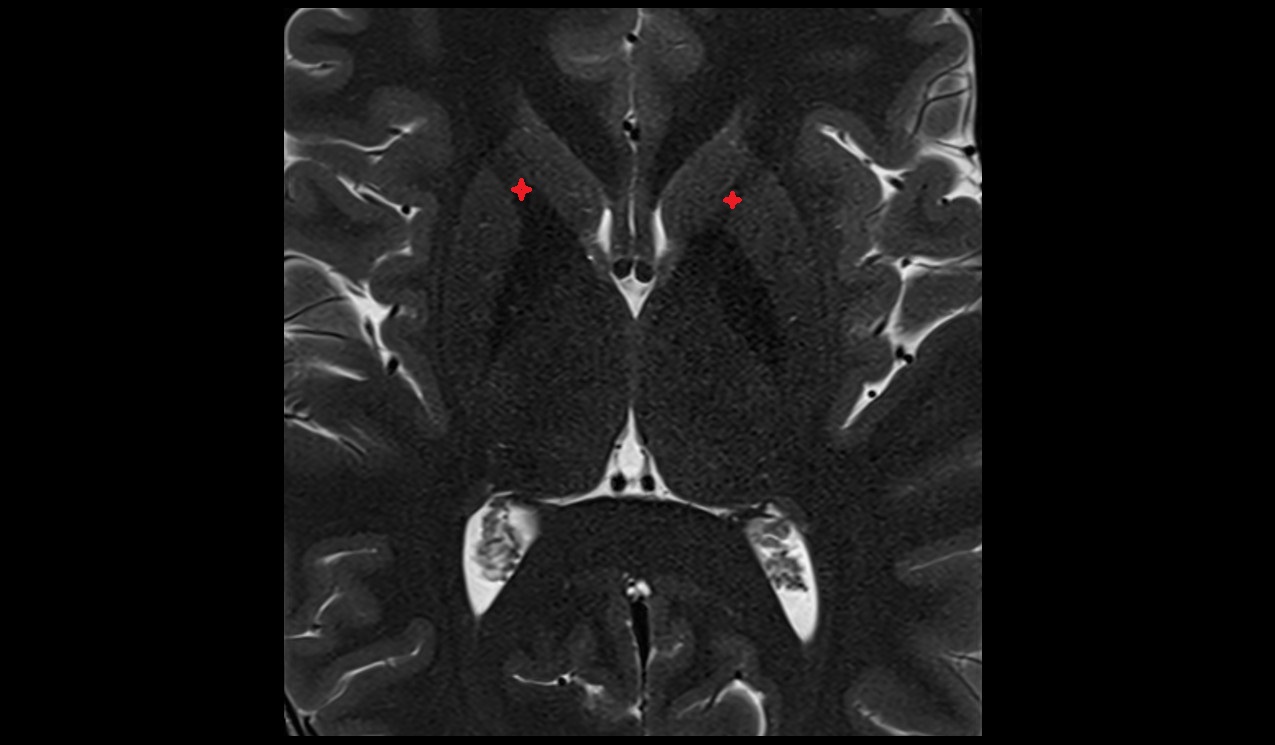

- Atrium of lateral ventricle

- Central part of lateral ventricle

- Frontal horn of lateral ventricle

- Temporal horn of lateral ventricle

- Third ventricle